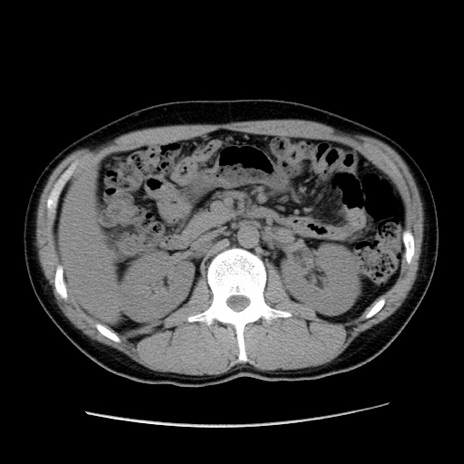

冠状断像

【症例】20歳代 男性

【主訴】心窩部痛

【現病歴】今朝より上腹部痛あり。一旦軽快していたが再度出現したため救急要請。昨日夕に白身の魚を含む刺身を食べた。

【身体所見】BP 136/89mmHg、HR 74/min、BT 37.0℃、腹部:膨満、軟、心窩部に圧痛あり。反跳痛なし、筋性防御なし、腸雑音やや亢進あり。

【データ】WBC 17700、CRP 0.48